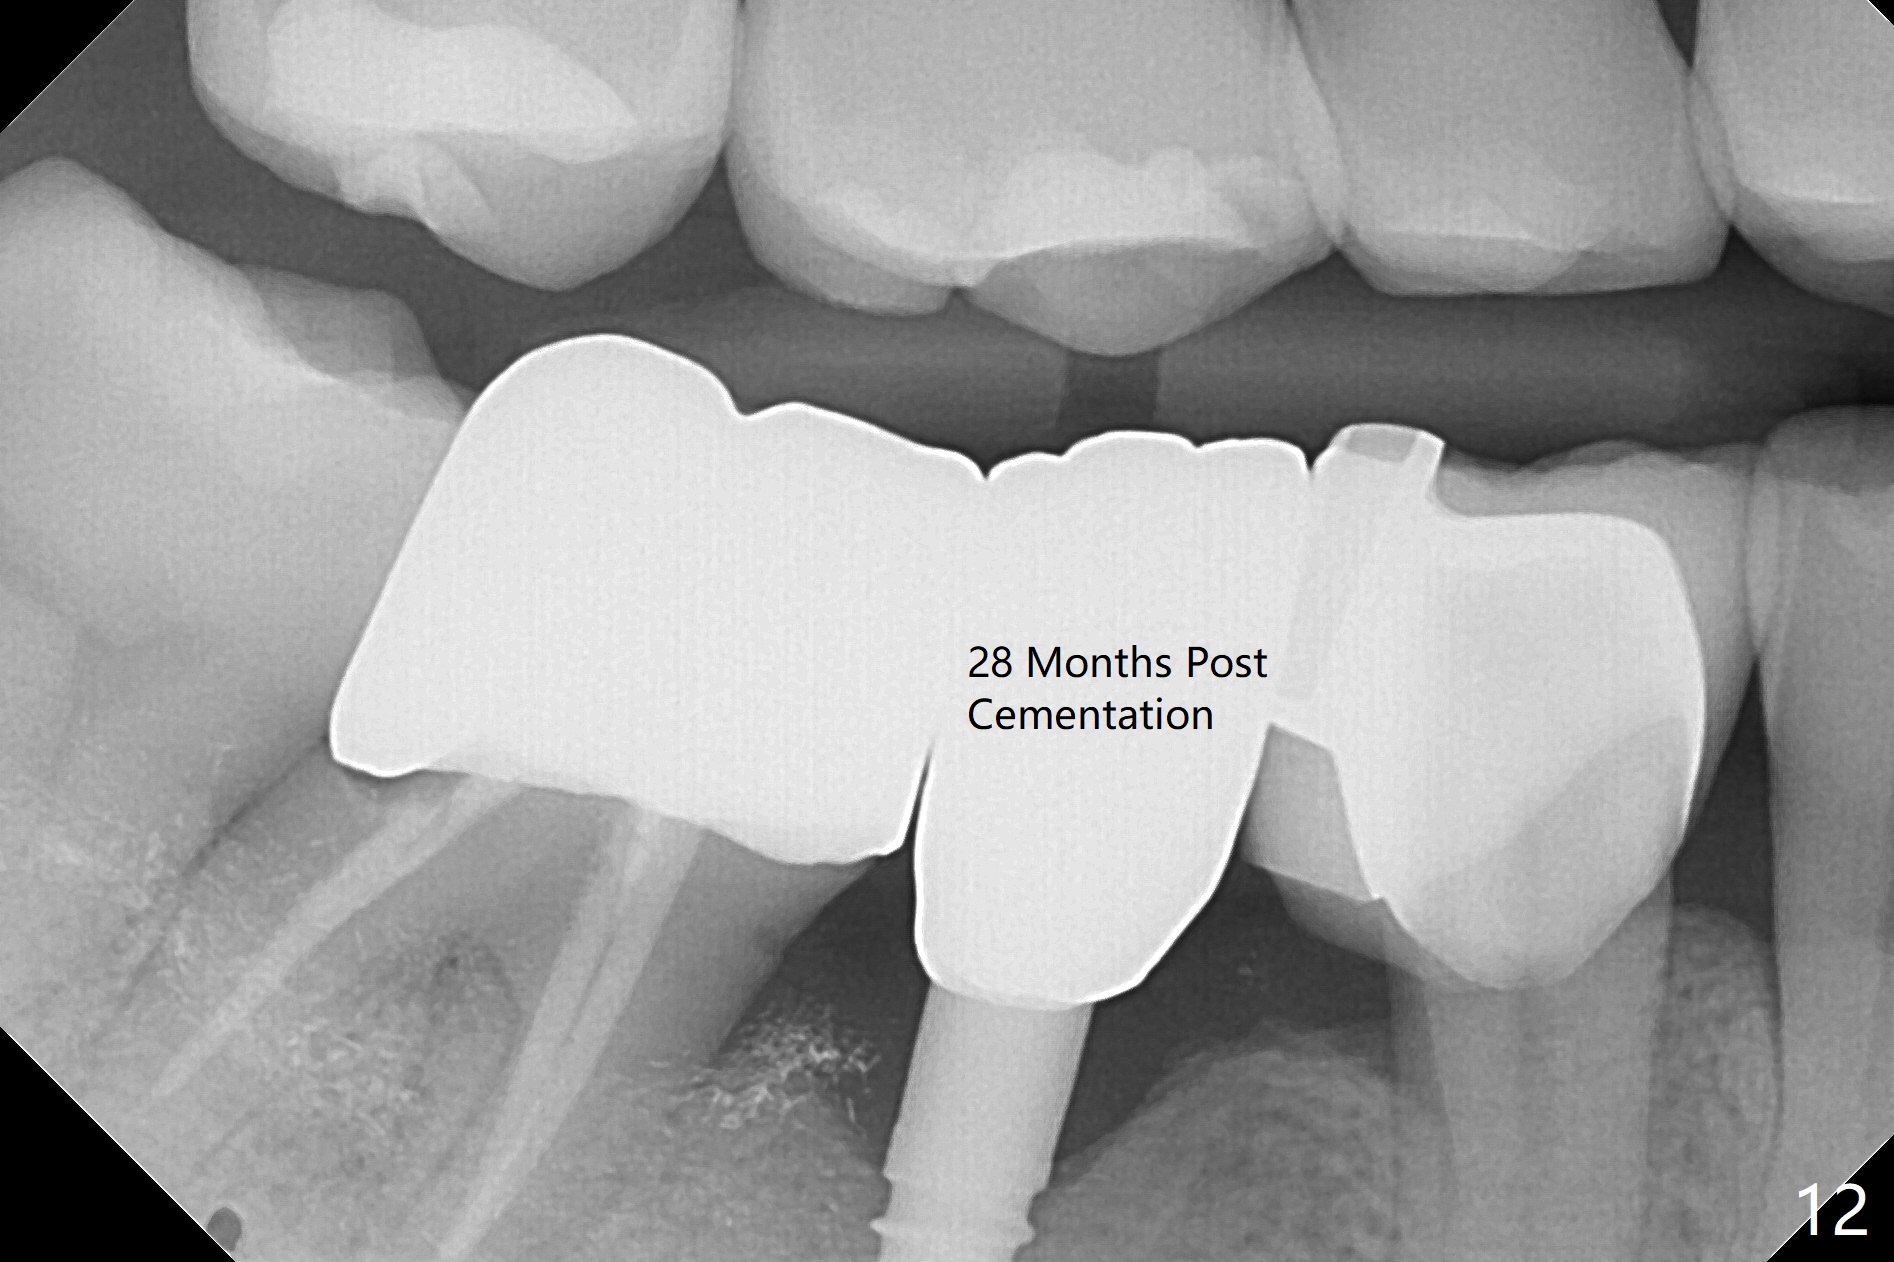

There is a space underneath the pontic at #30 (Fig.1 *), the basis for food impaction. After sectioning between the pontic and the posterior retainer, the pontic is removed from the anterior retainer with an attachment (Fig.2 *). The initial depth of osteotomy is 10 mm following ridge top reduction (Fig.3). A 3x10(4) mm 1-piece implant is placed with >50 Ncm; to reduce possibility of crown dislodgement from the implant, the retainers will be kept with modification of the proximal surfaces as shown by curved lines in Fig.4. Periodontal dressing is applied after suturing. There is no postop paresthesia. The periodontal dressing remains in place 2 weeks postop because of engagement into the attachment slot and undercuts (Fig.5). The patient returns 3 months postop; after minor contour adjustment (Fig.6 red curved line), impression is taken. The permanent crown is temporarily cemented (3.5 months postop) in case of food impaction due to the distal overhang of the tooth #29 (Fig.7). In fact the patient returns 4.5 months post cementation with right TMD (muscle relaxant prescribed) and food impaction, although there is no bone resorption (Fig.8,9). It appears that the crown at #29 needs to be redone, while porcelain will be added to the mesial surface of the one at #30 (Fig.10 red lines). In fact the crown at #30 is redone because of loose proximal contact with #31; there is no bone resorption 13 months post cementation (Fig.11). Bone resorption remains unnoticeable 28 months post cementation (Fig.12,13).